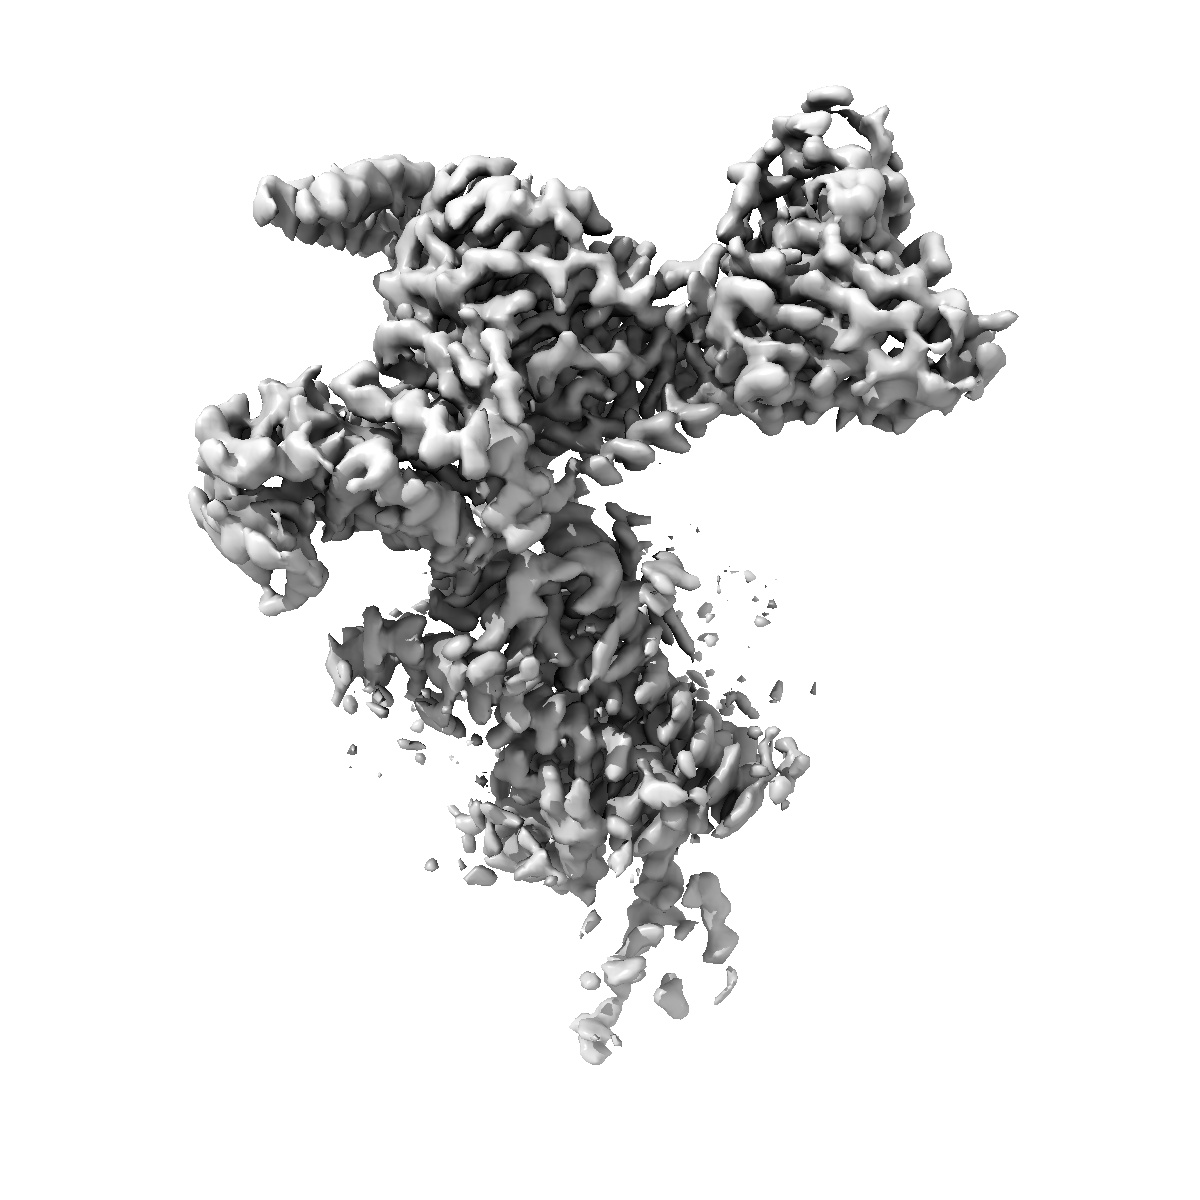

Cryo-EM structure of PTH-PTH1R-Gq complex (tilted state; consensus refinement map)

Single-particle2.77 Å

Sample: PTH-PTH1R-Gq complex

Insights into G-protein coupling preference from cryo-EM structures of G q -bound PTH1R.

(2025) Nat Chem Biol , 21 , 1906 - 1914